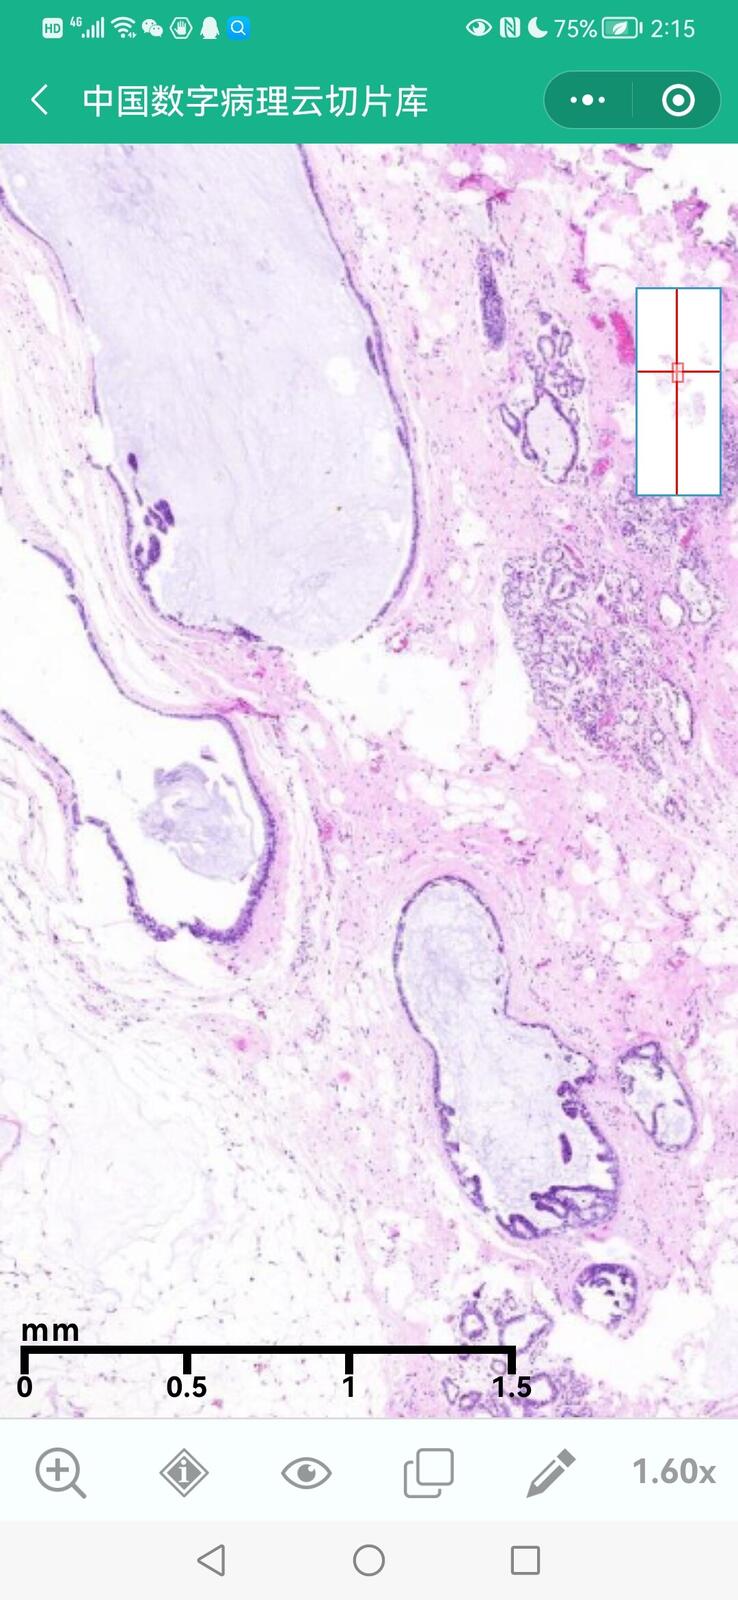

乳腺黏液性囊腺瘤伴导管内癌